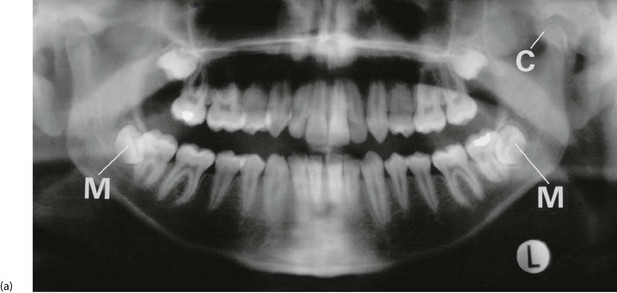

This occurs when a lower third molar (wisdom tooth) is impacted against the second molar or the ramus of the mandible so that its eruption is prevented (see Fig. 48.6). If a flap (operculum) of gingiva partly overlies the impacted tooth, this creates a space around the buried tooth crown (Fig. 48.6b). Food and bacterial plaque collect and cause acute infection, which may extend outwards, even into the parapharyngeal area.

Various cystic lesions and tumours arise in the jaws. Many are abnormalities of tooth-forming epithelium, developmental or acquired. Figure 48.9b shows a mandibular dentigerous cyst, a developmental cyst. They are rare and can usually be diagnosed radiologically. The jaws are occasionally the site of benign or malignant bone tumours such as osteosarcoma and osteoclastomas. They can also be affected by metastatic tumours from breast or prostate. Bony growth disorders such as fibrous dysplasia and Paget's disease may also affect the jaw.

Fig. 48.9 Dental cyst and dentigerous cyst

(a) Large dental cyst in the mandible. This arose from tooth-forming epithelial remnants in the apical area of the lower left second premolar tooth which was extracted several months beforehand due to chronic periapical infection. (b) Dentigerous cyst associated with the crown of an unerupted lower third molar. These cysts originate from epithelial remnants of the tooth bud